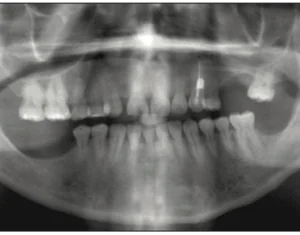

INTRODUCTION The introduction of cone-beam computed tomography (CBCT) scanners for the oral and maxillofacial region in the late 1990s has revolutionized dentistry. CBCT technology provides

Body Abstract New diagnostic technology that improves patient care is becoming more common in dental practices at both the generalist and specialist levels. However,